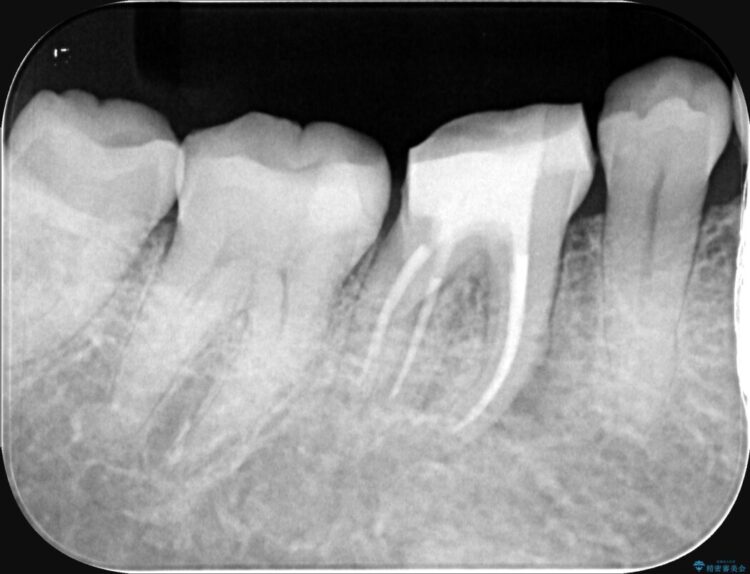

精密検査の結果、根の先に大きな病変が認められますが、根管内が狭窄し湾曲しているため、非常に難易度の高いケースです。

次に、根のカーブに沿ってしなやかに曲がるニッケルチタンファイルを使い、根の先まで徹底的に洗浄・殺菌を行いました。汚れを完全に取り除いた後、隙間なくお薬を詰めて密閉しています。

術後の経過は非常に良く、あんなに大きかった膿の袋は消え、健康な骨が再生しているのが確認できました。痛みや腫れも消えて抜歯を免れ、現在は被せ物を入れてしっかりお食事を楽しんでいただけるようになっています。